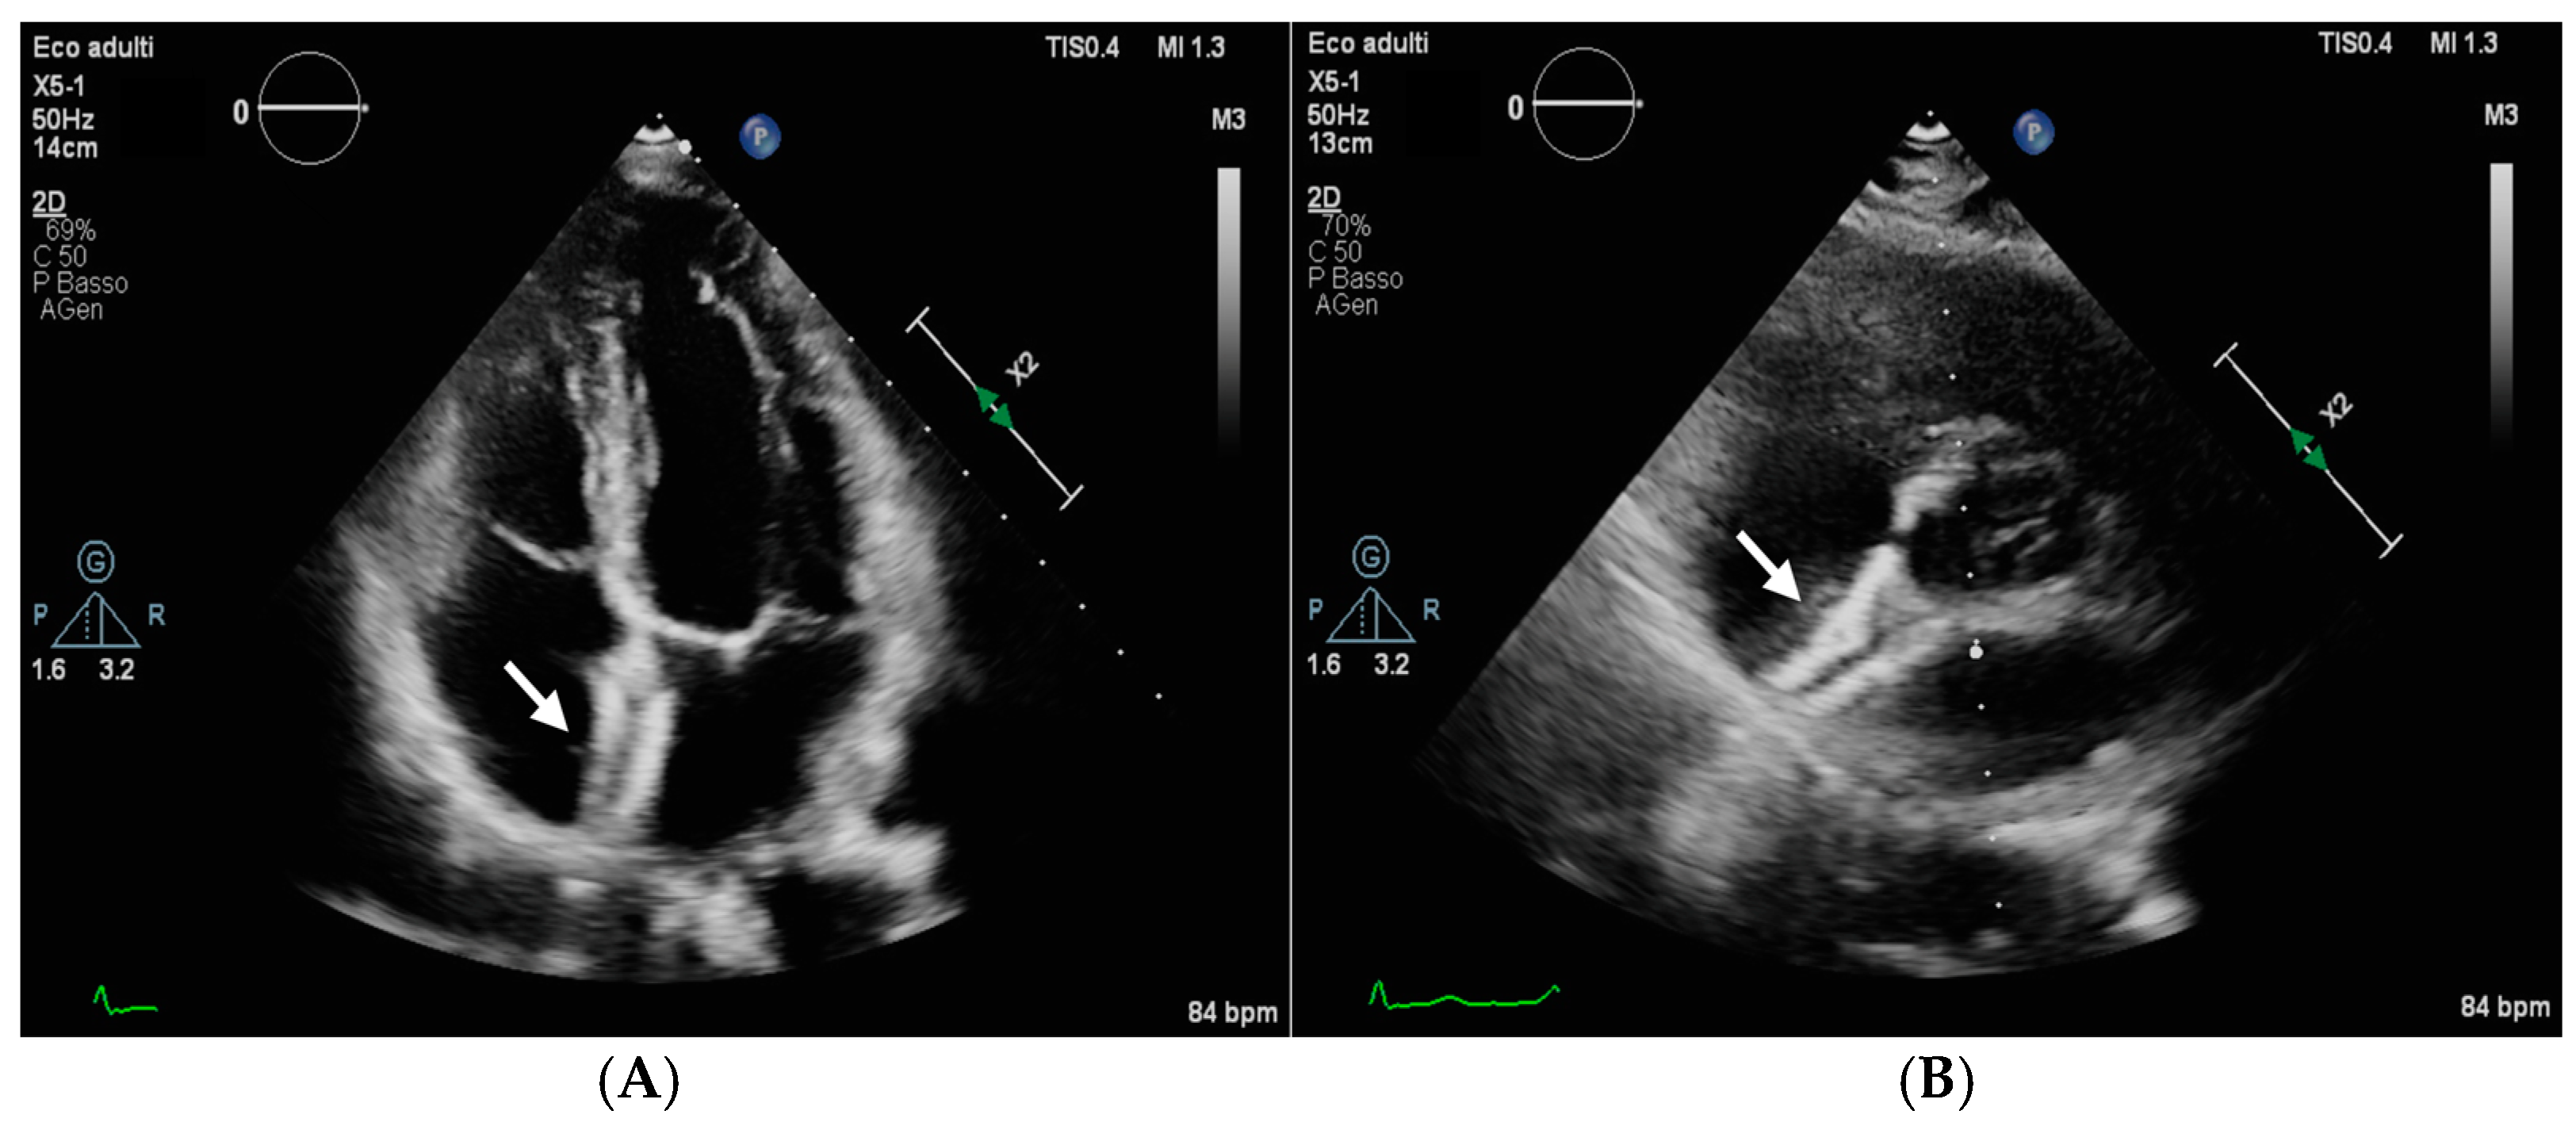

- Muratori, M.; Agostoni, P.; Trabattoni, D. When a patent foramen ovale device is no more in place: Silent patent foramen ovale occluder device migration to the aortic arch. Eur. Heart J. Case Rep. 2018, 3, 153. [Google Scholar] [CrossRef]